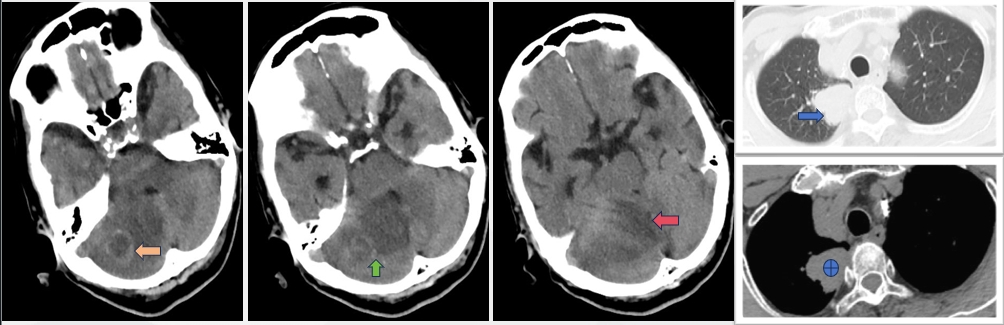

- 头CT(2024-5-8 我院)显示右侧小脑可见片状低密度影,其中类圆形低密度病灶周围可见高密度环状改变,建议增强扫描以除外占位性病变;胸部CT(2024-5-9 我院)提示右侧肺门较大占位,考虑肺癌,检验穿刺活检!

三、临床诊断

头晕(小脑传导通路异常,肺癌伴右侧小脑肿瘤转移)